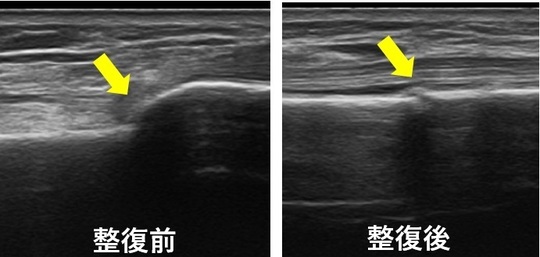

エコー観察を行い整復(骨折部を元に戻す操作)をして転位が改善している様子を確認します。

超音波観察画像

左が整復前、右が整復後。

骨折部が転位している様子が確認できます。

整復後には転位は元に戻っています。